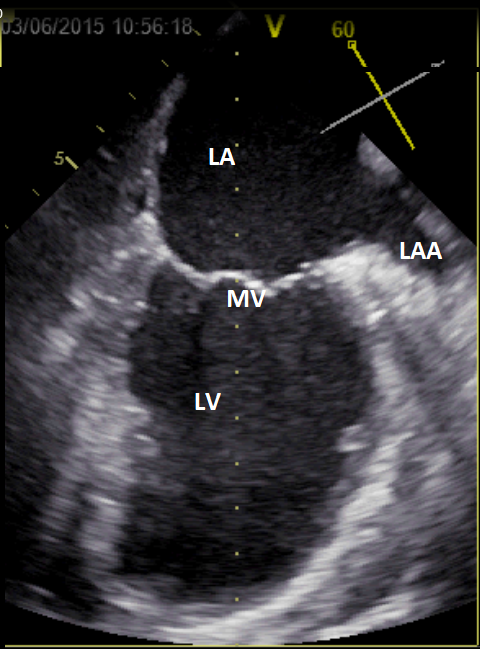

Figuur B – Slokdarmechocardiografie, 2-kamer opname linkerventrikel. LV=linkerventrikel. LA=linkeratrium, MV=mitralisklep, LAA=linker hartoor